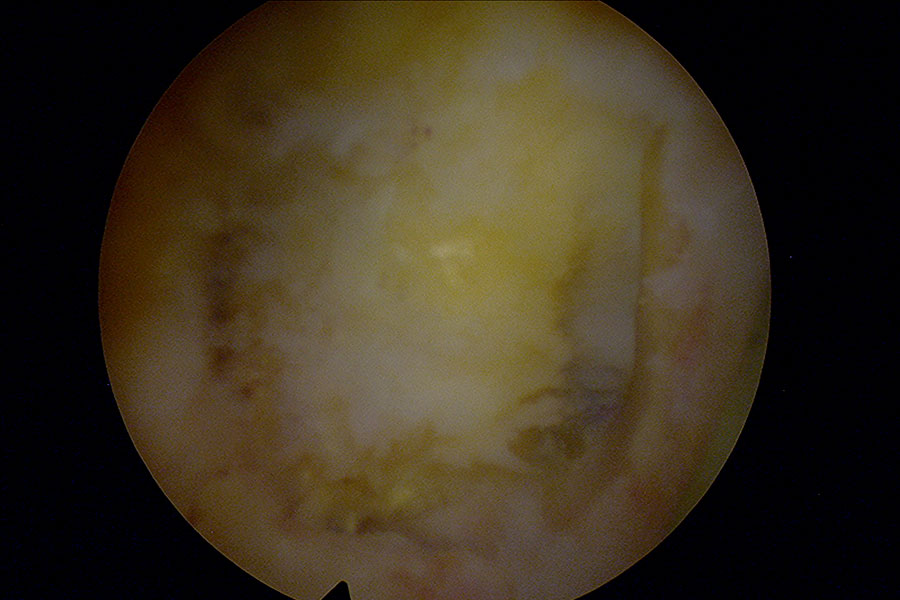

Tras una operación de columna, la paciente presenta una masa blanquecina que se decide retirar mediante técnica avanzada de endoscopia de columna